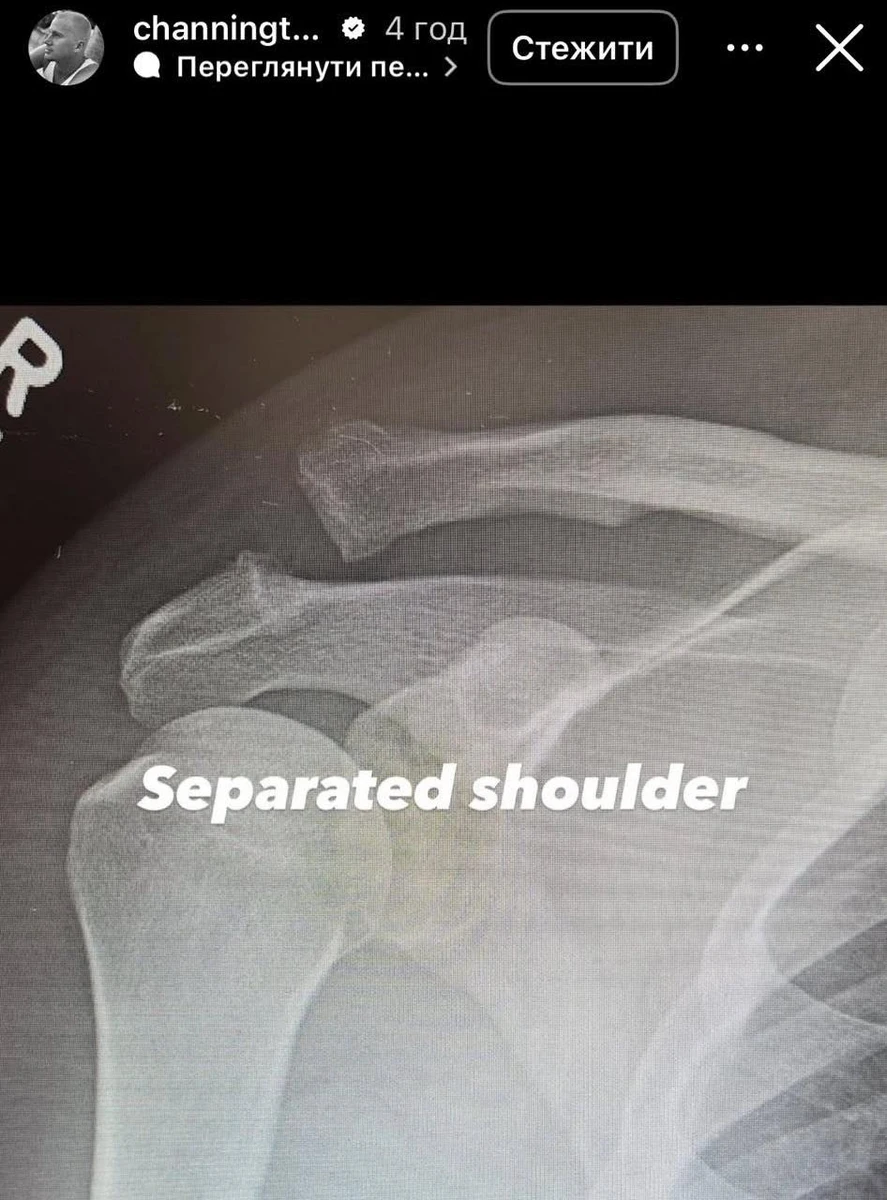

У сторіс Татум показав два свої рентгенівські знімки: до і після хірургічного втручання.

Виглядає боляче

"Плече скріпили гвинтом. Ура", - написав Татум